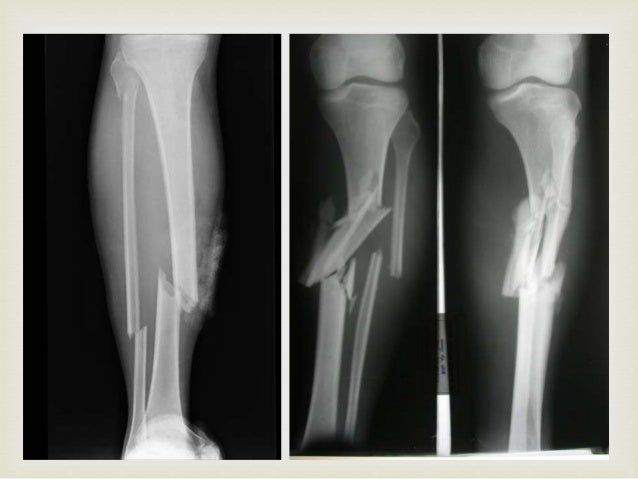

Fractura tibia y Perone 417 envíos / 0 nuevos Inicie sesión o regístrese para comentar Último envío Sáb, 22/11/08 1909 #1 pato Offline Registrado 22/11/08 1904 Fractura tibia y Perone Hola a todos Por lo que veo compartimos las mismas inquietudes!. La tibia se fractura en el tercio medio con el inferior, y se asocia con fractura de peroné en el tercio superior CONMINUTA Tiene muchos fragmentos pequeños Se produce cuando la pierna recibe un fuerte impacto estando apoyado el pie. Cuando hay una fractura de tibia y peroné que es lo suficientemente fuerte como para romper los huesos pero no lo suficientemente fuerte como para que los huesos penetren fuera de la piel es lo que llamamos fractura cerrada de tibia o fíbula En la mayoría de los casos de fractura de la parte inferior de las piernas, tanto la tibia como el.

Proceso completo de rehabilitacion de una fractura de tibia y perone, hasta poder caminar y el hueso haya sanado#TeamWorker. 70% son de tibia aisladas Son fracturas espiroídeas u oblicuas FRACTURAS DIAFISIARIAS DE TIBIA Y PERONE 29 angulada tercio medio 30 31 *En niños Si peroné integro Se previene el acortamiento No se desplaza 60% presentará Varo en las primeras 2 semanas Fracturas diafisiarias de Tibia 32 Valgo tras fractura de tibia 33. Horas previas a la intervención quirúrgica.

Las fractura abiertas tipo IIIBIIIC de tibia, con o sin peroné, suponen el grado más severo de la clasificación de Gustilo (1) Las fracturas grado IIIB se caracterizan por una interrupción de la vascularización tibial y un daño severo de las partes blandas circundantes, con una alta tasa de complicaciones. CIE10 código S2 para Fractura de la diáfisis de la tibia definiciones en línea español. La tibia se fractura en el tercio medio con el inferior, y se asocia con fractura de peroné en el tercio superior CONMINUTA Tiene muchos fragmentos pequeños Se produce cuando la pierna recibe un fuerte impacto estando apoyado el pie.